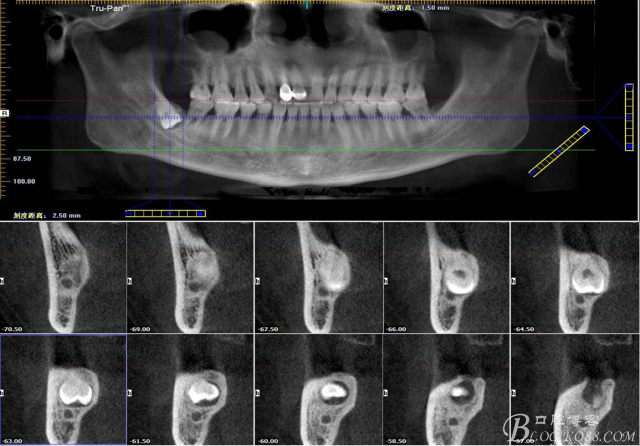

二、術前CBCT影像:

48未萌出,47遠中可探及深約7mm的牙周袋。頰側47、48之間牙齦紅腫,有少量血性滲出。X線根尖片顯示:48牙冠反轉倒置,47遠中牙槽骨吸收明顯。CBCT顯示:48牙冠近中面位于下頜管內。

圖1. 47牙冠的近中面緊鄰下頜神經管

圖2.判斷47牙根是否吸收

圖3.通過矢狀面和冠狀面來判斷48與下頜管及47的關系

圖4.水平方向48與47之間的關系

圖6.測量48頰、舌側骨板厚度。

圖7.測量牙冠近遠中徑的大小及遠中骨板的厚度